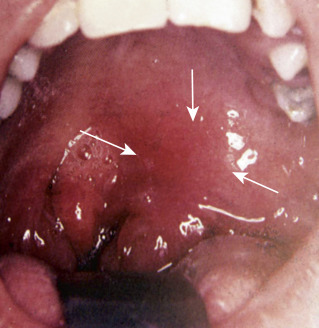

Contributor: Ricky Dhaliwal, MD Educational Pearls: Angioedema in anaphylaxis Histamine and mast cell-mediated pathway Treatment: First line: epinephrine for vasoconstriction and bronchodilation Second line: H1 and H2 antihistamines such as Benadryl and famotidine ACE inhibitor-induced angioedema Different pathway from anaphylaxis ACE inhibitor-induced angioedema is mediated by bradykinins Therefore, anaphylaxis medications are not beneficial in patients with ACE inhibitor-induced angioedema Leading cause of drug-induced angioedema in the US Patients most commonly present with swelling of the lips, tongue, or face Treatment: Airway management: varies depending on the severity and progression of the presentation If awake nasointubation is required, LMX is a 5% lidocaine water-soluble solution that provides anesthesia to the oropharynx Medications: Icatibant is a synthetic bradykinin B2-receptor antagonist that can be used in acute treatment Tranexamic acid (TXA) inhibits the plasmin-dependent formation of bradykinin, but the data on this treatment are mixed and limited Fresh frozen plasma (FFP) is thought to degrade high levels of bradykinin with subsequent resolution of angioedema Discontinue ACE inhibitor References Bork K, Wulff K, Hardt J, Witzke G, Staubach P. Hereditary angioedema caused by missense mutations in the factor XII gene: clinical features, trigger factors, and therapy. J Allergy Clin Immunol. 2009 Jul;124(1):129-34. doi: 10.1016/j.jaci.2009.03.038. Epub 2009 May 27. PMID: 19477491. Bova M, Guilarte M, Sala-Cunill A, Borrelli P, Rizzelli GM, Zanichelli A. Treatment of ACEI-related angioedema with icatibant: a case series. Intern Emerg Med. 2015 Apr;10(3):345-50. doi: 10.1007/s11739-015-1205-9. Epub 2015 Feb 10. PMID: 25666515. Karim MY, Masood A. Fresh-frozen plasma as a treatment for life-threatening ACE-inhibitor angioedema. J Allergy Clin Immunol. 2002 Feb;109(2):370-1. doi: 10.1067/mai.2002.121313. PMID: 11842313. Pathak GN, Truong TM, Chakraborty A, Rao B, Monteleone C. Tranexamic acid for angiotensin-converting enzyme inhibitor-induced angioedema. Clin Exp Emerg Med. 2024 Mar;11(1):94-99. doi: 10.15441/ceem.23.051. Epub 2023 Aug 1. PMID: 37525579; PMCID: PMC11009700. Simons FE. First-aid treatment of anaphylaxis to food: focus on epinephrine. J Allergy Clin Immunol. 2004 May;113(5):837-44. doi: 10.1016/j.jaci.2004.01.769. Erratum in: J Allergy Clin Immunol. 2004 Jun;113(6):1039. Dosage error in article text. PMID: 15131564. Summarized by Meg Joyce, MS2 | Edited by Meg Joyce & Jorge Chalit, OMS4 Donate: https://emergencymedicalminute.org/donate/